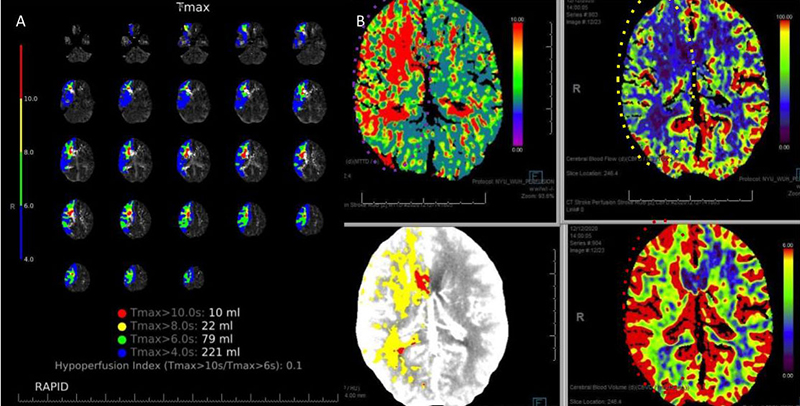

CT Brain Perfusion Imaging confirmed marked delay in contrast/blood Time to Peak (TMax) and Mean Transit Time (MTT) with decreased right hemispheric Cerebral Blood Flow and elevated Cerebral Blood Volume. These findings suggested that this critical right ICA stenosis resulted in significant hemodynamic perfusion failure and ischemia within the right hemispheric territories of the right MCA and ACA vascular distributions (Figure 2). No large vessel intracranial occlusion requiring emergent thrombectomy was observed, and the mild initial symptomatic presentation favored further imaging and medical optimization prior to revascularization attempts.

Figure 2. A) CT Brain Prefusion Tmax confirms delayed flow; B) MTT, CBF, CBV and Hybrid Threshold Parametric Maps of Right MCA/ACA revealing diminished CBF, elevated CBV, and prolonged MTT of at-risk Ischemic Tissue.